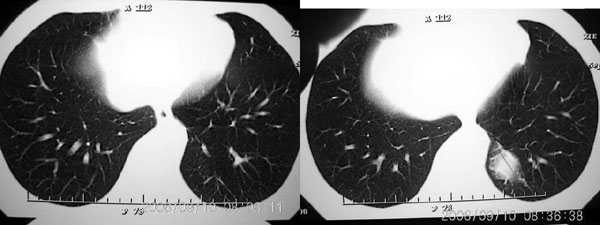

左侧脊柱旁沟可见一边界清,密度不均匀之块状影,其内可见水样低密度影。

2、病变位于左肺下叶后段,周围肺组织相对干净,没有明显异常的改变,基本可以排除炎性病变;病变实质内密度均匀,边缘清晰,后下缘与膈脚分界不清晰。各征象均支持肺隔离症。

左肺下野后侧基底段见结节状肿块影,边界清晰锐利,其内见低密度坏死灶,紧贴胸膜生长,深分叶征不明显,纵隔内无明显肿大淋巴结,临床无咯血病史,所有征像均不支持恶性病变。病变考虑为纵隔内病变,没有增强扫描,定性很困难。

把选定的图像复制到woad,左键双击--图片设计格式--图片--亮度,调整亮度(到60--70)即可见到病灶血管与降主动脉相连,即病灶由降主动脉供血.